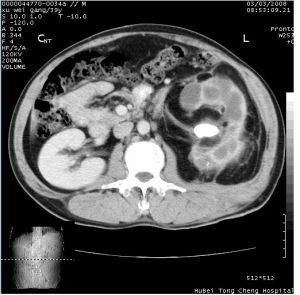

4.CT檢查 可顯示腎實質中形態不�一、邊緣模糊的混合密度腫塊,中央為低密度。增強掃描示腎實質增強明顯降低,腎盂腎盞不顯影。